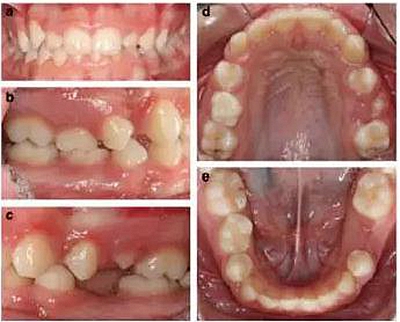

患者 女 13歲

患者面型對稱,面上下比例對稱,輕度凸面型,鼻唇角正常;

輕度牙齦炎,口腔衛(wèi)生一般,無齲??;

右側(cè)II類磨牙關(guān)系和尖牙關(guān)系,左側(cè)I類磨牙關(guān)系和尖牙關(guān)系;

深覆合,前牙輕度不齊,下中線右偏2mm;

上下頜右側(cè)第二乳磨牙存,其余乳磨牙已脫落;